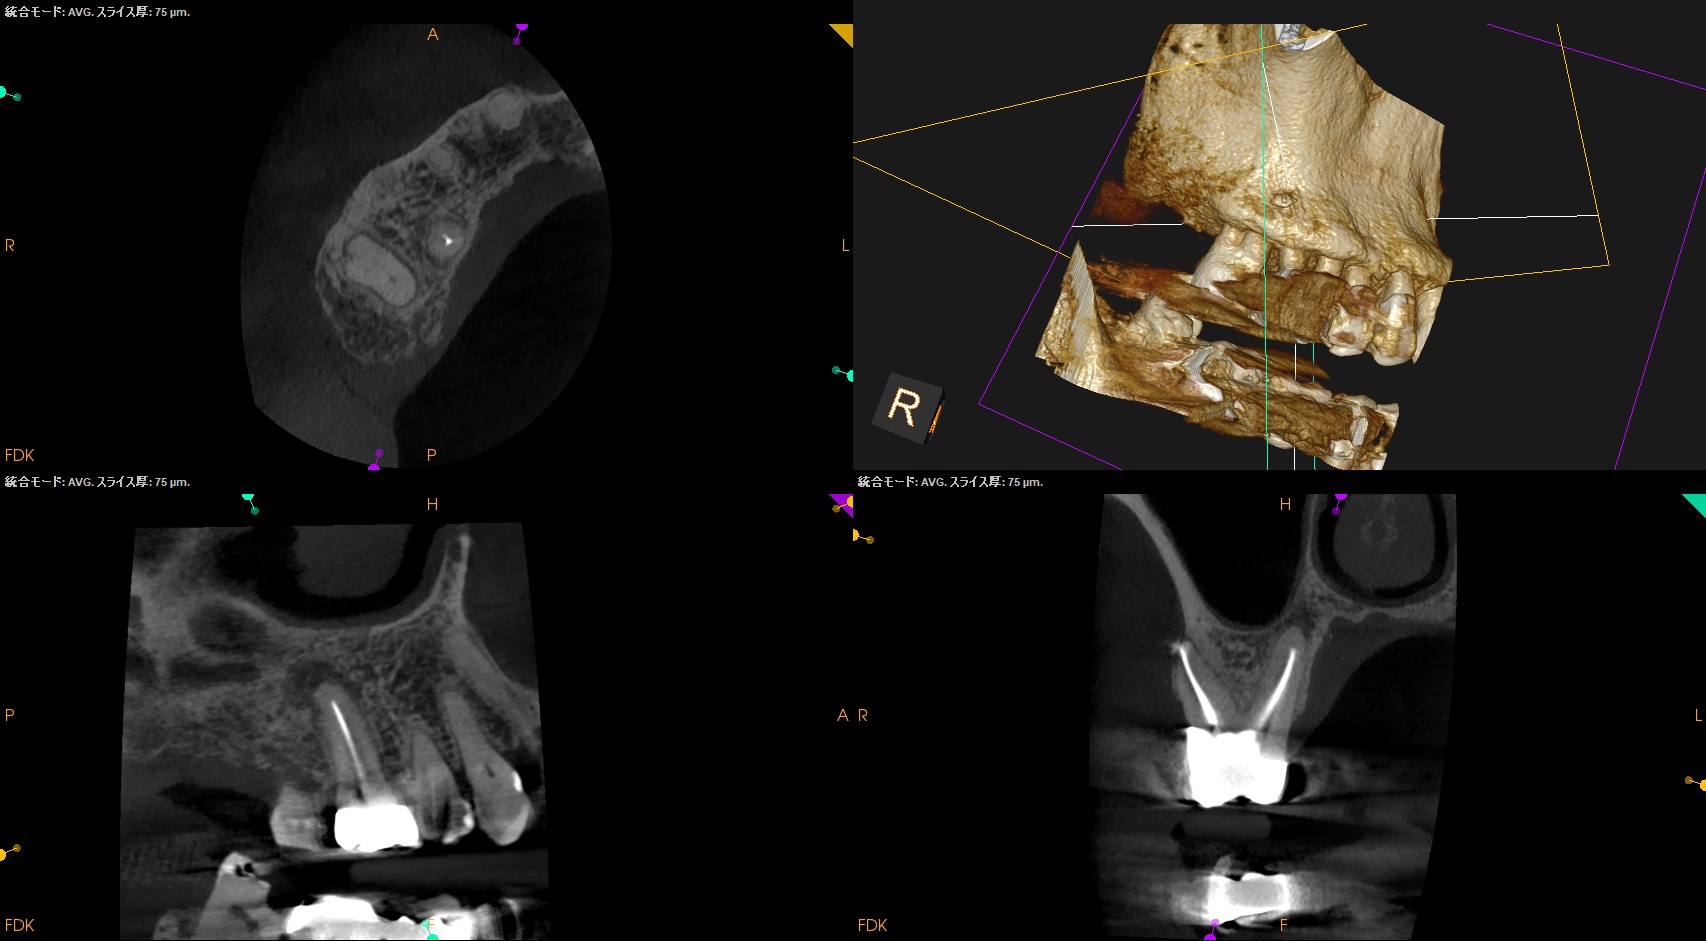

#3 RCT 1yr recall(2026.1.5)

DBの歯槽骨はまだ回復中(Healiing)だが臨床症状は消失した。

ということでまた来年も経過を見ることとなった。